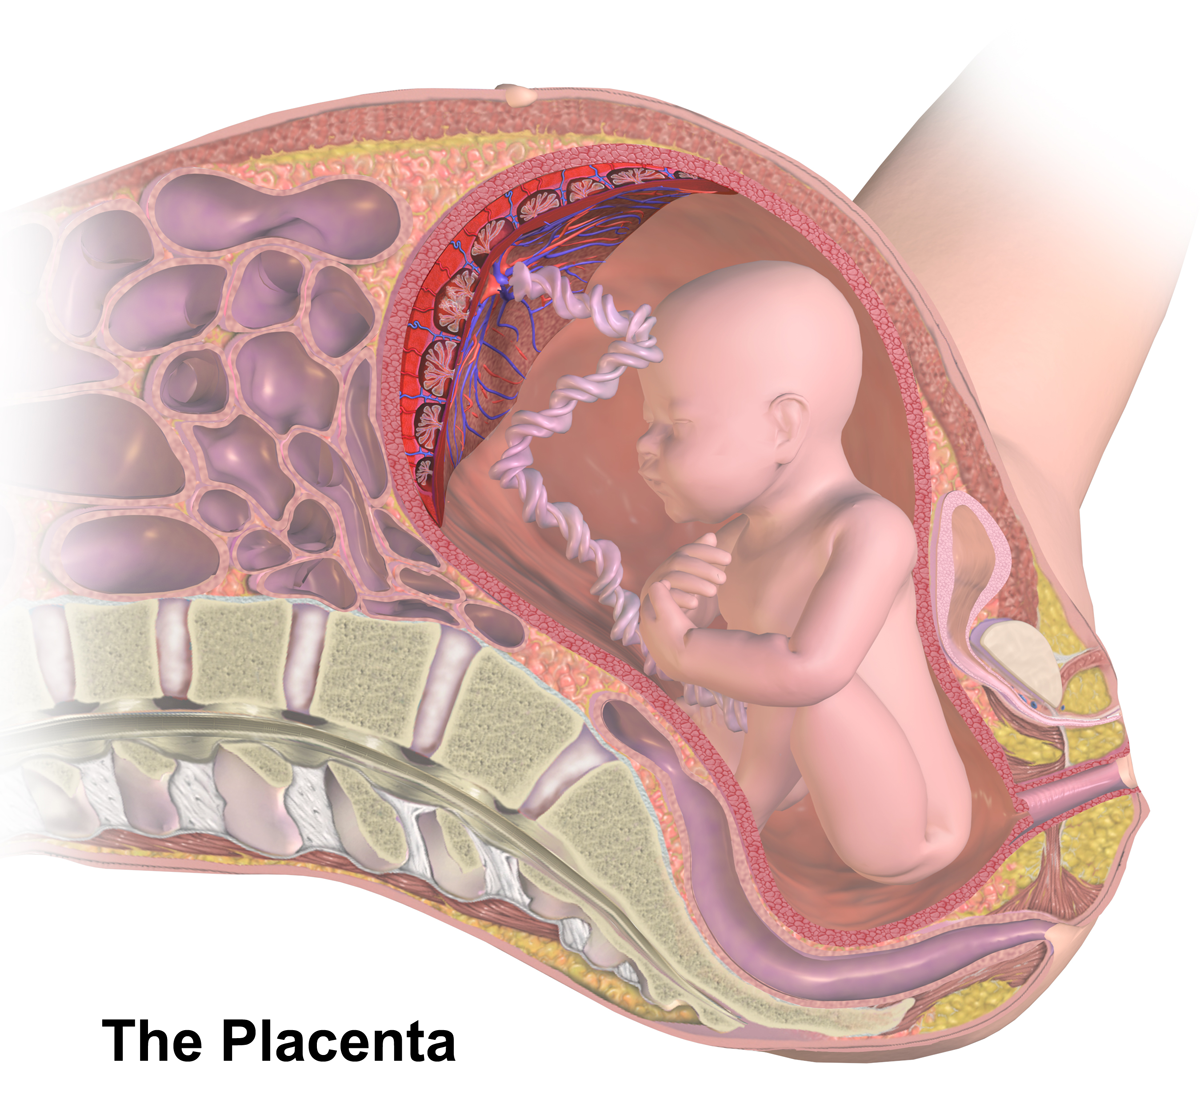

Околоплодный пузырь и плацента: структура и функции